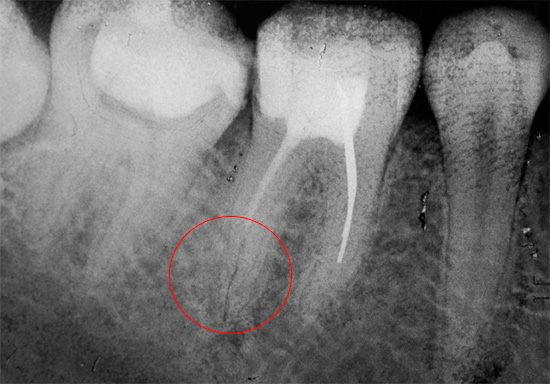

Por exemplo, os erros mais comuns no tratamento da pulpite fibrosa são o preenchimento insuficiente dos canais dentários. O padrão de qualidade para o tratamento de canais permite o preenchimento de todo o comprimento com firmeza e o ápice - constrição fisiológica. Se o canal não estiver selado na marca indicada, no futuro poderá haver grandes problemas associados à ativação da infecção nos vazios do canal. É especialmente perigoso quando o canal é apenas 20-50% selado.

É mais difícil corrigir o erro associado à remoção do preenchimento de material intracanal além da raiz.Às vezes, esse erro vale a saúde do paciente se o material penetrar profundamente no seio maxilar (ao tratar os canais do dente superior) ou no canal mandibular (ao tratar o dente inferior).

Nesses casos, o material de enchimento removido atua como um corpo estranho, irritando os tecidos e provocando fortes dores. A sinusite se desenvolve no seio maxilar e a neurite no canal maxilar. A ajuda oportuna na forma de intervenção cirúrgica por um dentista-cirurgião para extrair o excesso de material economiza saúde e, muitas vezes, vida ao paciente. Por razões óbvias, um dente com essa complicação geralmente precisa ser removido para fornecer melhor acesso a materiais estranhos.